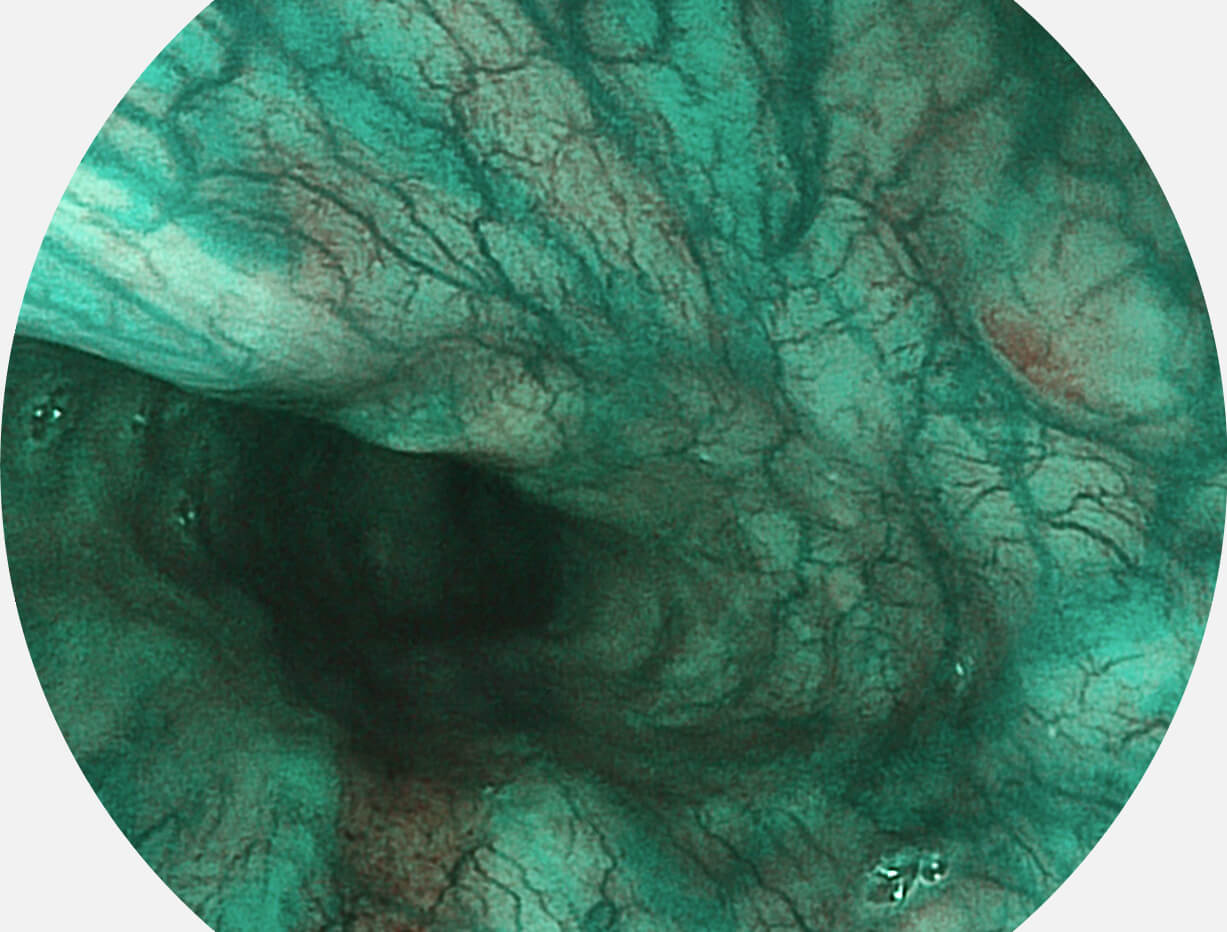

光电复合染色成像技术

Versatile Intelligent Staining Technology, VIST

强调浅层黏膜结构的同时,保证照明亮度和提升浅层微血管与中层血管颜色对比度,病变边界更清晰。

• 白光图像 VIST图像